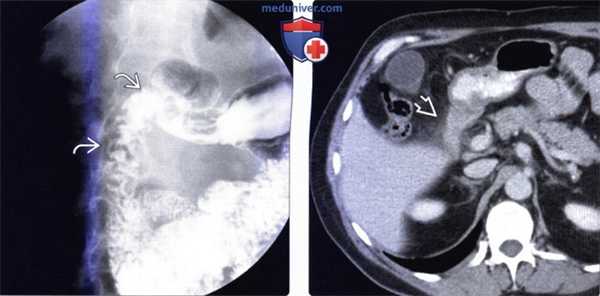

(Слева) На рентгенограмме визуализируются множественные маленькие полиповидные образования в проксимальных отделах двенадцатиперстной кишки. При исследовании биоптата, полученного при эндоскопическом исследовании, были обнаружены признаки гиперплазии, а также выявлены элементы гамартомы, возникшей из Бруннеровых желез.

(Справа) На рентгенограмме (кадр из рентгеноскопического исследования) определяется полиповидное объемное образование в луковице двенадцатиперстной кишки. После эндоскопической биопсии и резекции подтвердилась гамартома Бруннеровой железы. Большие, изолированные поражения, как в этом случае, неотличимы от множества других объемных образований дуоденальной луковицы; при их обнаружении требуется биопсия.